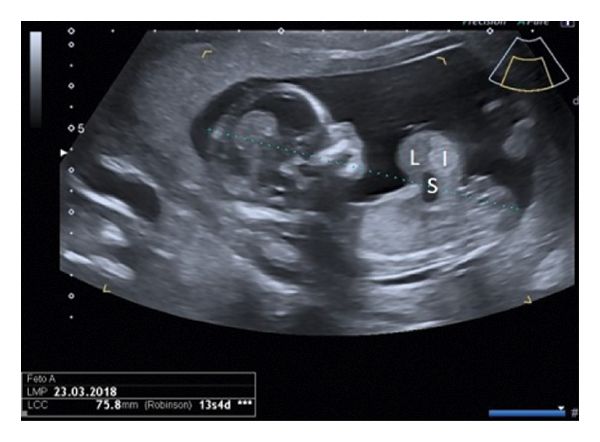

Омфалоцеле можно диагностировать во время беременности с помощью ультразвукового исследования (УЗИ). Двумерное УЗИ позволяет обнаружить патологию на 14–18-й неделе беременности, трёхмерное — в более раннем периоде. При выполнении исследования омфалоцеле выглядит как округлое или овальное образование, которое заполнено органами брюшной полости (петлями кишечника, печенью) и примыкает к передней брюшной стенке.

![Омфалоцеле на УЗИ [13] Омфалоцеле на УЗИ [13]](/media/bolezny/omfalocele/omfalocele-na-uzi-13_s.jpeg)

Омфалоцеле на УЗИ [13]

Чтобы подтвердить, что орган находится за пределами брюшной полости, при УЗИ используется доплеровское картирование. Это метод визуализации тока крови, он основан на определении скорости кровотока в сосудах органа с применением разных цветов.

В большинстве беременностей, которые сопровождаются омфалоцеле у плода, в крови у женщин обнаруживается повышение уровня сывороточного альфа-фетопротеина. Он является маркером патологии плода, например дефекта нервной трубки или дефекта передней брюшной стенки (в том числе омфалоцеле) [9]. Но эти патологии намного эффективнее выявляются с помощью УЗИ, поэтому сейчас анализ на альфа-фетопротеин необязательный для беременных [14].